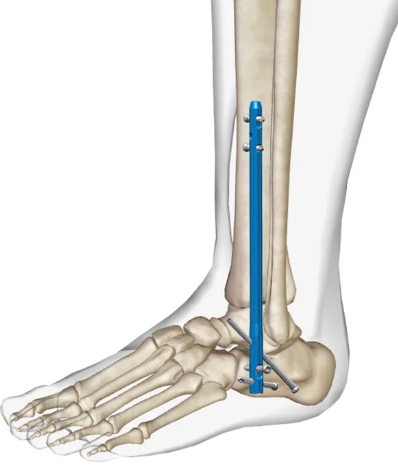

В случае перелома шейки бедра компания МосРентген Центр госпитализирует в Склиф для эндопротезирования.